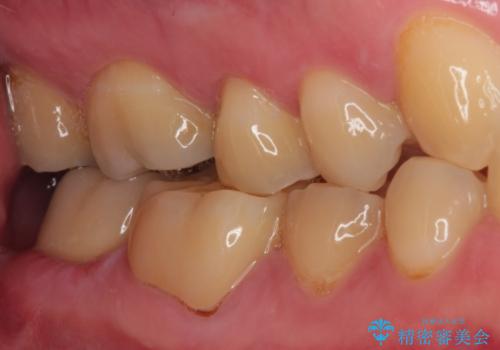

- 東南アジアへの長期赴任を前に、以前から気になっていたむし歯を治療したいとのことで来院された患者様です。

レントゲン写真から、神経の近くにまでむし歯が及んでいる様子が分かり、範囲も広範囲であったので、まずは仮歯に置き換え、その後オールセラミッククラウンにて補綴治療を行うこととしました。

処置を開始するに当たり検査診断を行ったところ、歯髄組織にまでむし歯が及んでいる可能性が示唆されたため、万が一の事態に備えてラバーダム装着による無菌的環境にて虫歯除去を行うこととしました。

虫歯は歯髄組織のギリギリにまで及んでいたものの、歯髄組織が露出することはなく、処置から数日経った日に行った検査でも歯髄組織の異常所見は認めれらませんでした。

速やかに補綴治療を行い、無事に海外赴任前に治療を終えることができました。